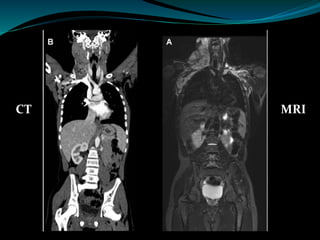

CT scans, or Computed Tomography scans, have long been a staple in medical diagnostics. However, recent studies and Urban's claims have shed light on potential risks associated with this technology. The primary concern revolves around radiation exposure. CT scans use X-rays to create detailed images of the body, which means patients are exposed to ionizing radiation.

On the other hand, Magnetic Resonance Imaging (MRI) uses powerful magnets and radio waves to create detailed images of the body's internal structures. Unlike CT scans, MRIs do not use ionizing radiation, which makes them a seemingly safer option. However, Urban's claims suggest that there might be hidden dangers associated with MRI technology as well.